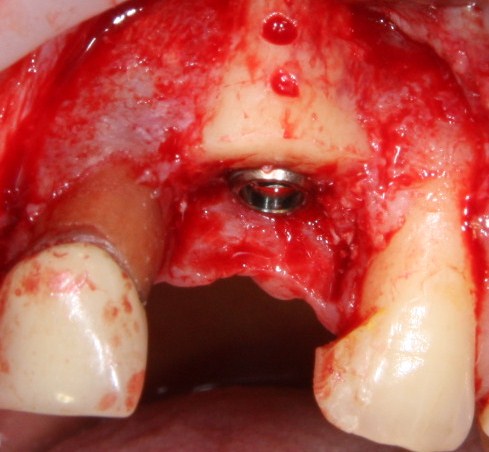

Трансплантация десны, аугментация лунки

Для определения размеров будущего мягкотканного аутотрансплантата мы использовали пародонтологический зонд. С помощью него мы выбрали донорскую зону (бугор верхней челюсти или небная сторона альвеолярного отростка верхней челюсти в области моляров), с помощью скальпеля получили необходимый по размеру аутотрансплантат (мягкотканный лоскут для пересадки).

Затем, мы подготовили ксенографт Bio-Oss Collagen. Обычно на 2 зуба (центральных резца) с избытком хватает 100-миллиграмовой упаковки. Имеющийся в ней параллелепипед мы поделили на 2 усеченные пирамиды с основанием в 2/3 ширины изначального блока.

Если вы когда-нибудь видели подобные операции, то наверняка обращали внимание на порядок действий — сначала устанавливаются имплантаты, затем укладывается графт и только потом фиксируется мягкотканный аутотрансплантат. Для удобства в этом и похожих клинических ситуациях мы поменяли порядок действий:

Сначала мы провели и зафиксировали деэпителизированный соединительнотканный аутотрансплантат (ССТ). Для этого мы сформировали тоннель и использовали ортодонтическую проволоку в качестве проводника. Подробнее об этой методике можно почитать здесь>>.

Затем уложили ксенографт. Особенностями Bio-Oss Collagen являются удобство адаптации, устойчивость к вымыванию и выдавливанию, поэтому мы просто уложили полученные ранее пирамидки вестибулярно относительно будущего имплантата, после чего прижали их с помощью уже упоминавшихся аналогов имплантата, входящих в хирургический набор имплантационной системы Xive (кстати, при работе с другими имплантационными системами для паковки графта в лунке можно использовать круглые остеотомы для синуслифтинга).

В совокупности, аугментация лунок перед установкой имплантатов занимает около 20 минут — и это самый долгий из всех хирургических этапов лечения.